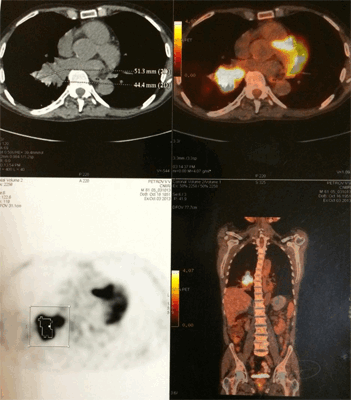

Диагноз «рак легкого» часто устанавливается на основании данных рентгенографии, компьютерной томографии (КТ), позитронной эмиссионной томографии (ПЭТ). В качестве синонимов этого диагноза специалисты лучевой диагностики нередко используют термины «новообразование», «Neo», «Са» и т.д. (рис. 1, рис.2, рис.3).

Рис. 1. Рис. ПЭТ-КТ всего тела - современный высокоточный метод диагностики рака легкого и определения степени распространенности опухоли.

Рис. 3. Позитронная эмиссионная томография пациента О., 72 лет с большой периферической опухолью верхней доли правого легкого. При биопсии - плоскоклеточный рак. При видеомедиастиноскопии - метастазов в лимфоузлах средостения не выявлено. В апреле 2007 года пациент успешно прооперирован в нашем Центре в объеме расширенной верхней лобэктомии справа. При контрольном осмотре в 2013 году состояние больного удовлетворительное признаков, рецидива опухоли нет.